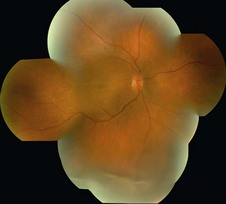

Patients with rhegmatogenous RD present with painless unilateral decrease in vision or visual field with flashes and floaters. Most eyes have a posterior vitreous detachment. Examination reveals elevation of the retina, with a corrugated appearance and generally clear subretinal fluid that does not shift with position. The pathognomonic sign of a rhegmatogenous RD is the presence of one or more retinal tears or full thickness holes (Fig. 24.1.1).

Figure 24.1.1 Color photograph shows a rhegmatogenous retinal detachment with a retinal tear. Note the corrugated, transparent retinal surface. The second photograph shows a serous retinal detachment.